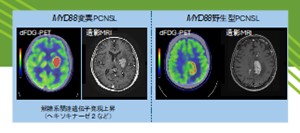

2025.07.30 脳悪性リンパ腫の遺伝子異常を判定する画像検査法を開発 最新型の半導体PET画像で可視化